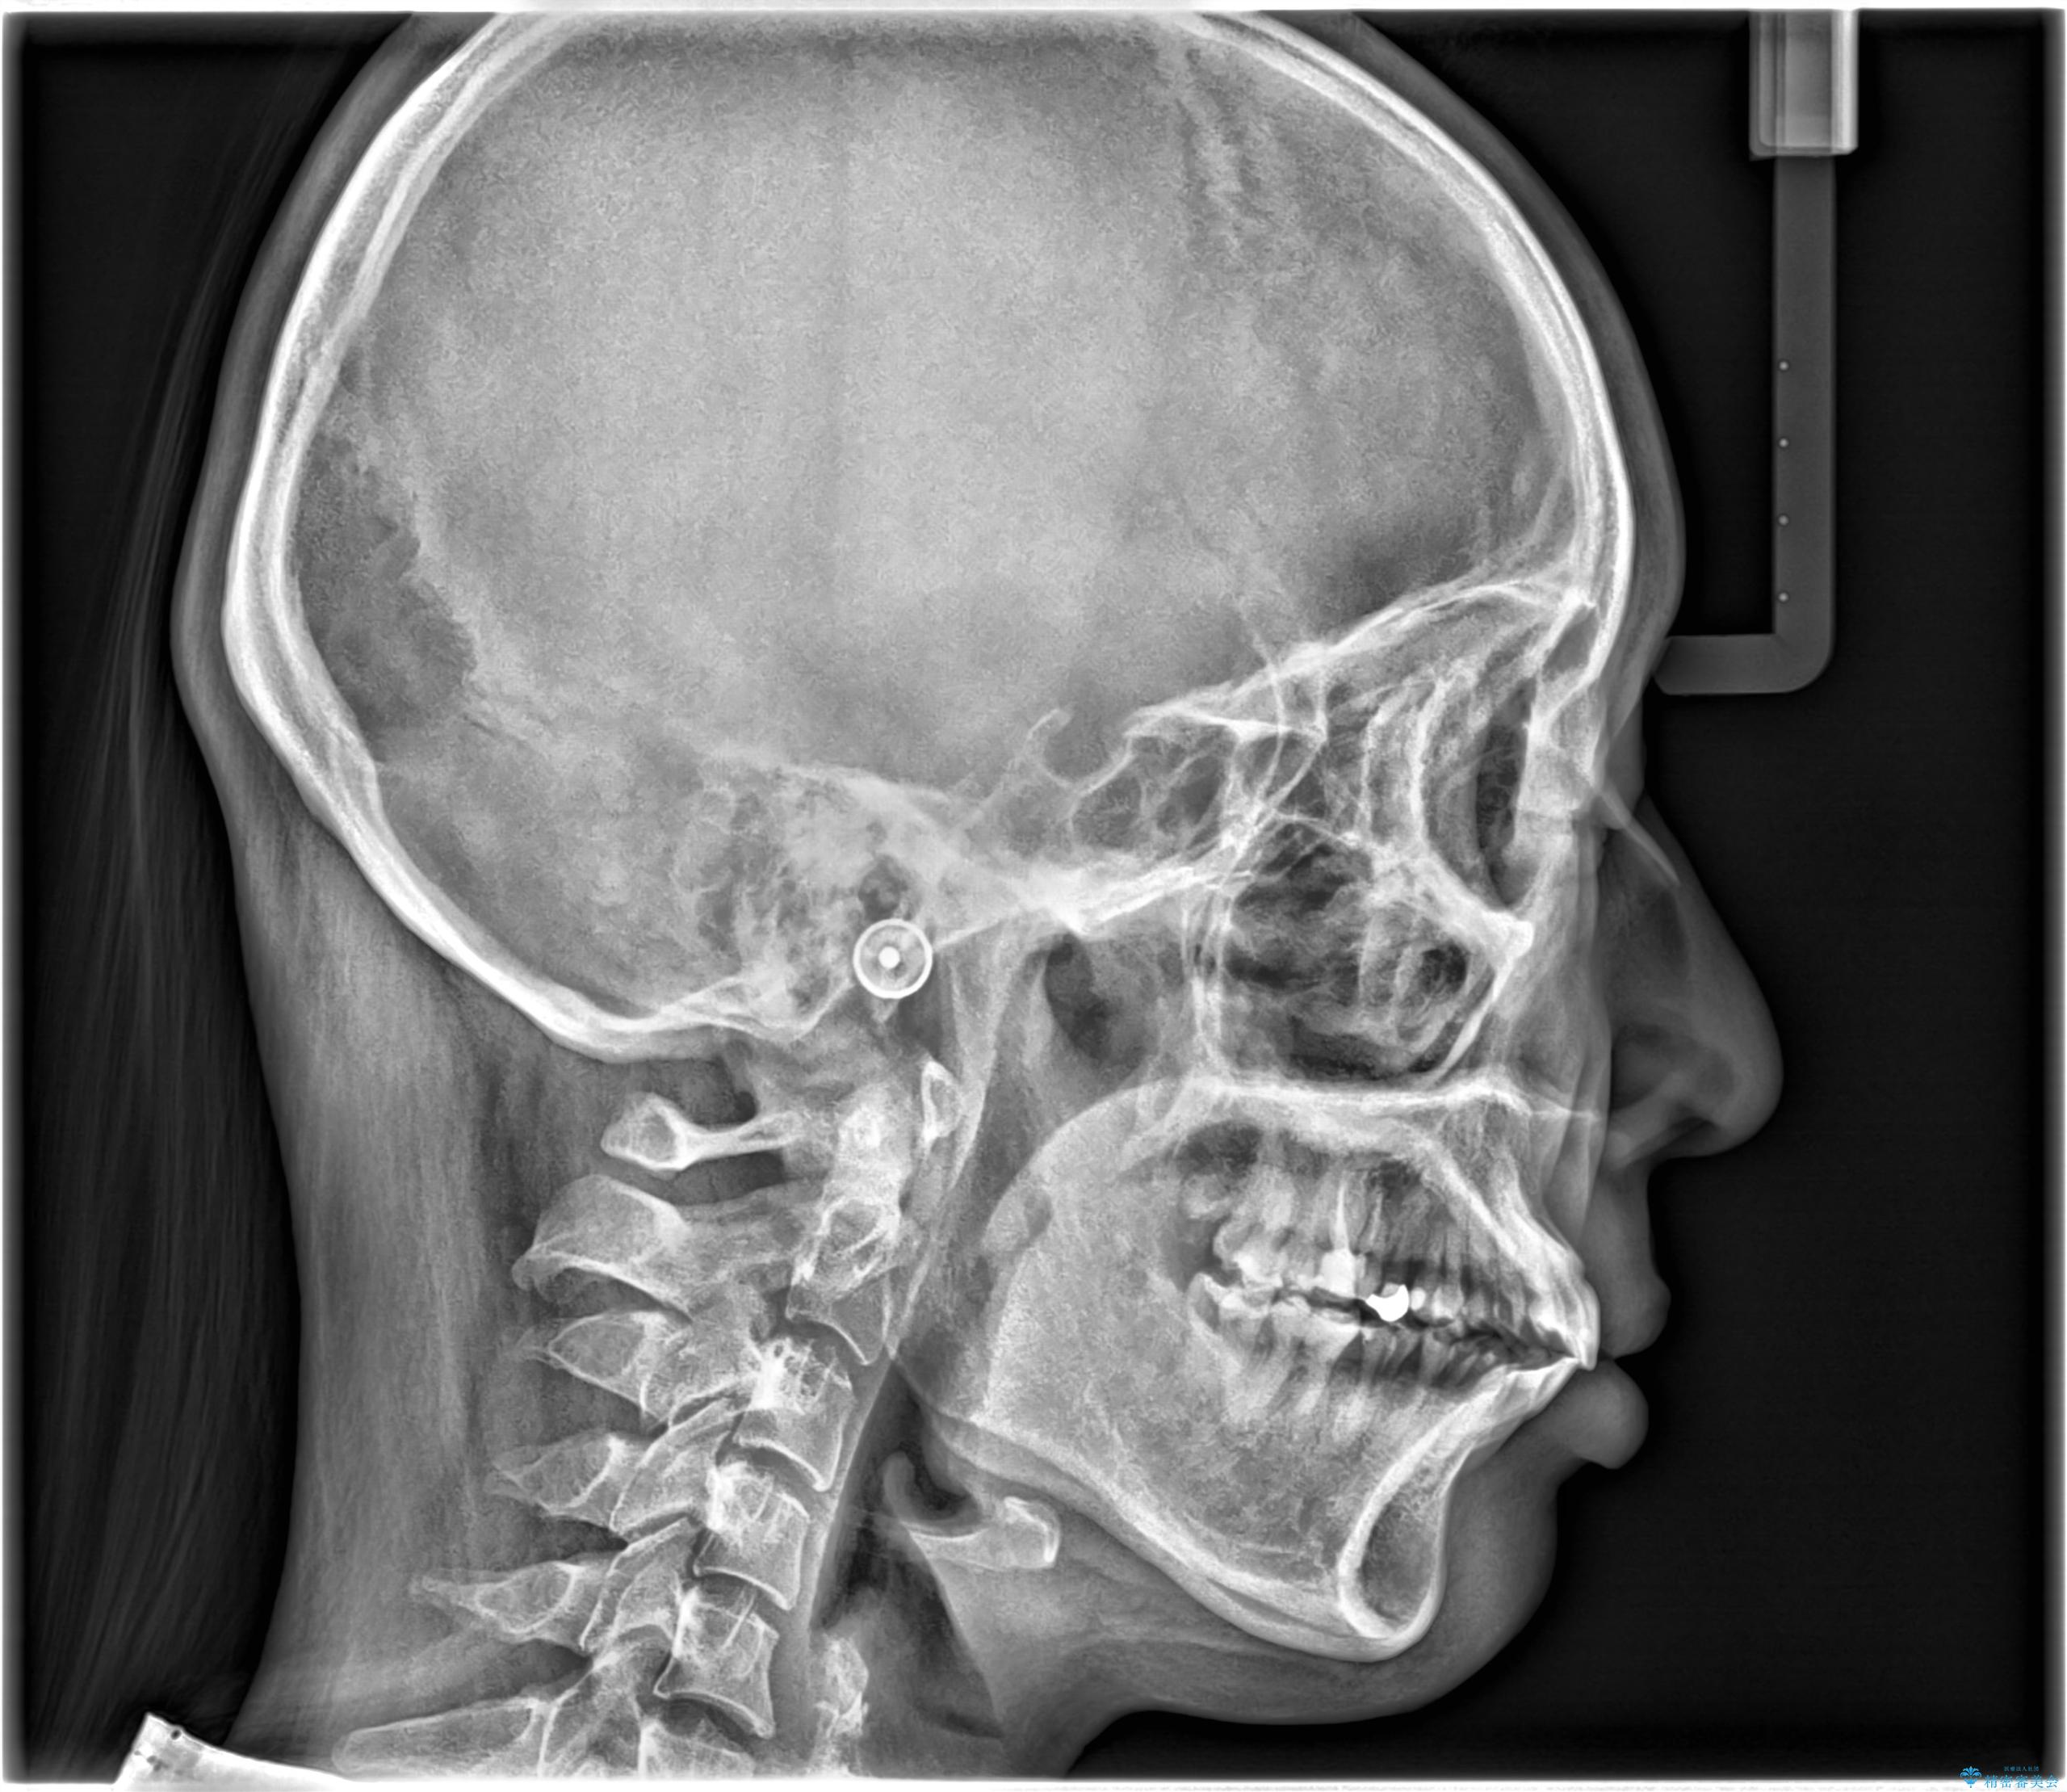

- 主訴:学生時代に矯正治療したが、後戻りしてしまった。上下前がのガタつきを治したい。

ワイヤー矯正(審美装置)非抜歯 治療期間:1年8か月

途中、大臼歯の遠心移動のためリンガルアーチを使用しています。